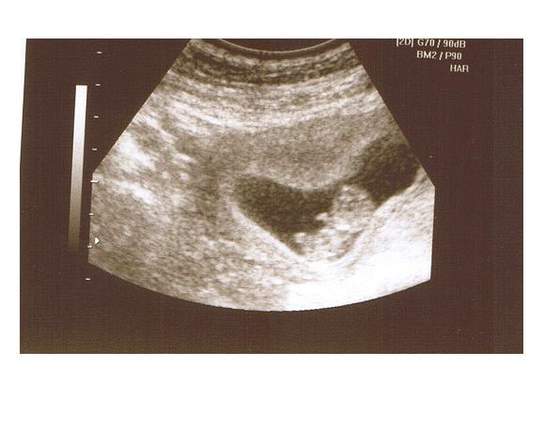

Zdjecie tez juz mam i o dziwo ja juz dzis mialam robione usg przez brzuszek;-)

A oto i nasz skarb!